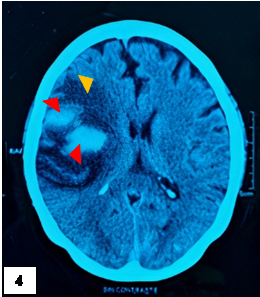

A las 3h, la escala NIHSS fue de 19 puntos, asociada a hemiplejía izquierda, lateralización de la mirada a la derecha y compromiso severo de conciencia. Se indicó una TEM cerebral sin contraste control, encontrándose foco isquémico en región parietal derecha, asociado a hemorragia subaracnoidea (figura 2). Luego de permanecer 7 horas en emergencia, ingresa a UCI. A las 12 horas se registra PA de 181/85 mmHg, asociado a taquicardia, taquipnea y febrícula (37,6°C). A las 24h se realiza una TEM cerebral y una angio-TEM que reveló un ECV isquémico con transformación hemorrágica post trombólisis, sin presencia de aneurisma roto (figura 3). La paciente permaneció en UCI en ventilación mecánica. A los 10 días, se realizó una TEM control que reveló menor volumen de hematoma en comparación al estudio tomográfico previo (figura 4). A los 20 días tras su ingreso a UCI fue dada de alta.

Amplia área isquémica (cabeza flecha roja) y zonas hiperdensas que corresponden al sangrado intraparenquimal a nivel parietal derecho (cabeza flecha naranja).